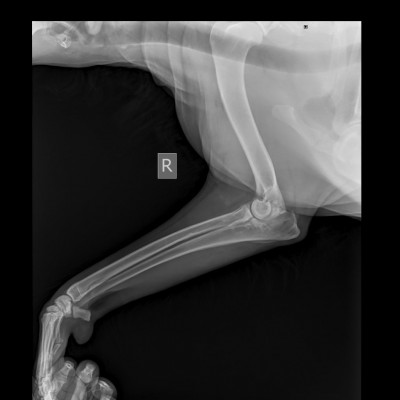

По локтю :

Крючковидный отросток фрагментирован, артрит.

Здесь по сути только НПВС курсами при обострении.

Это было понятно заранее.

С таким суставом Блэку жить.

Сустав отреагировал на 10 дней антибиотика лучше, чем на хондропротектор. Хромота заметно снизилась:))))